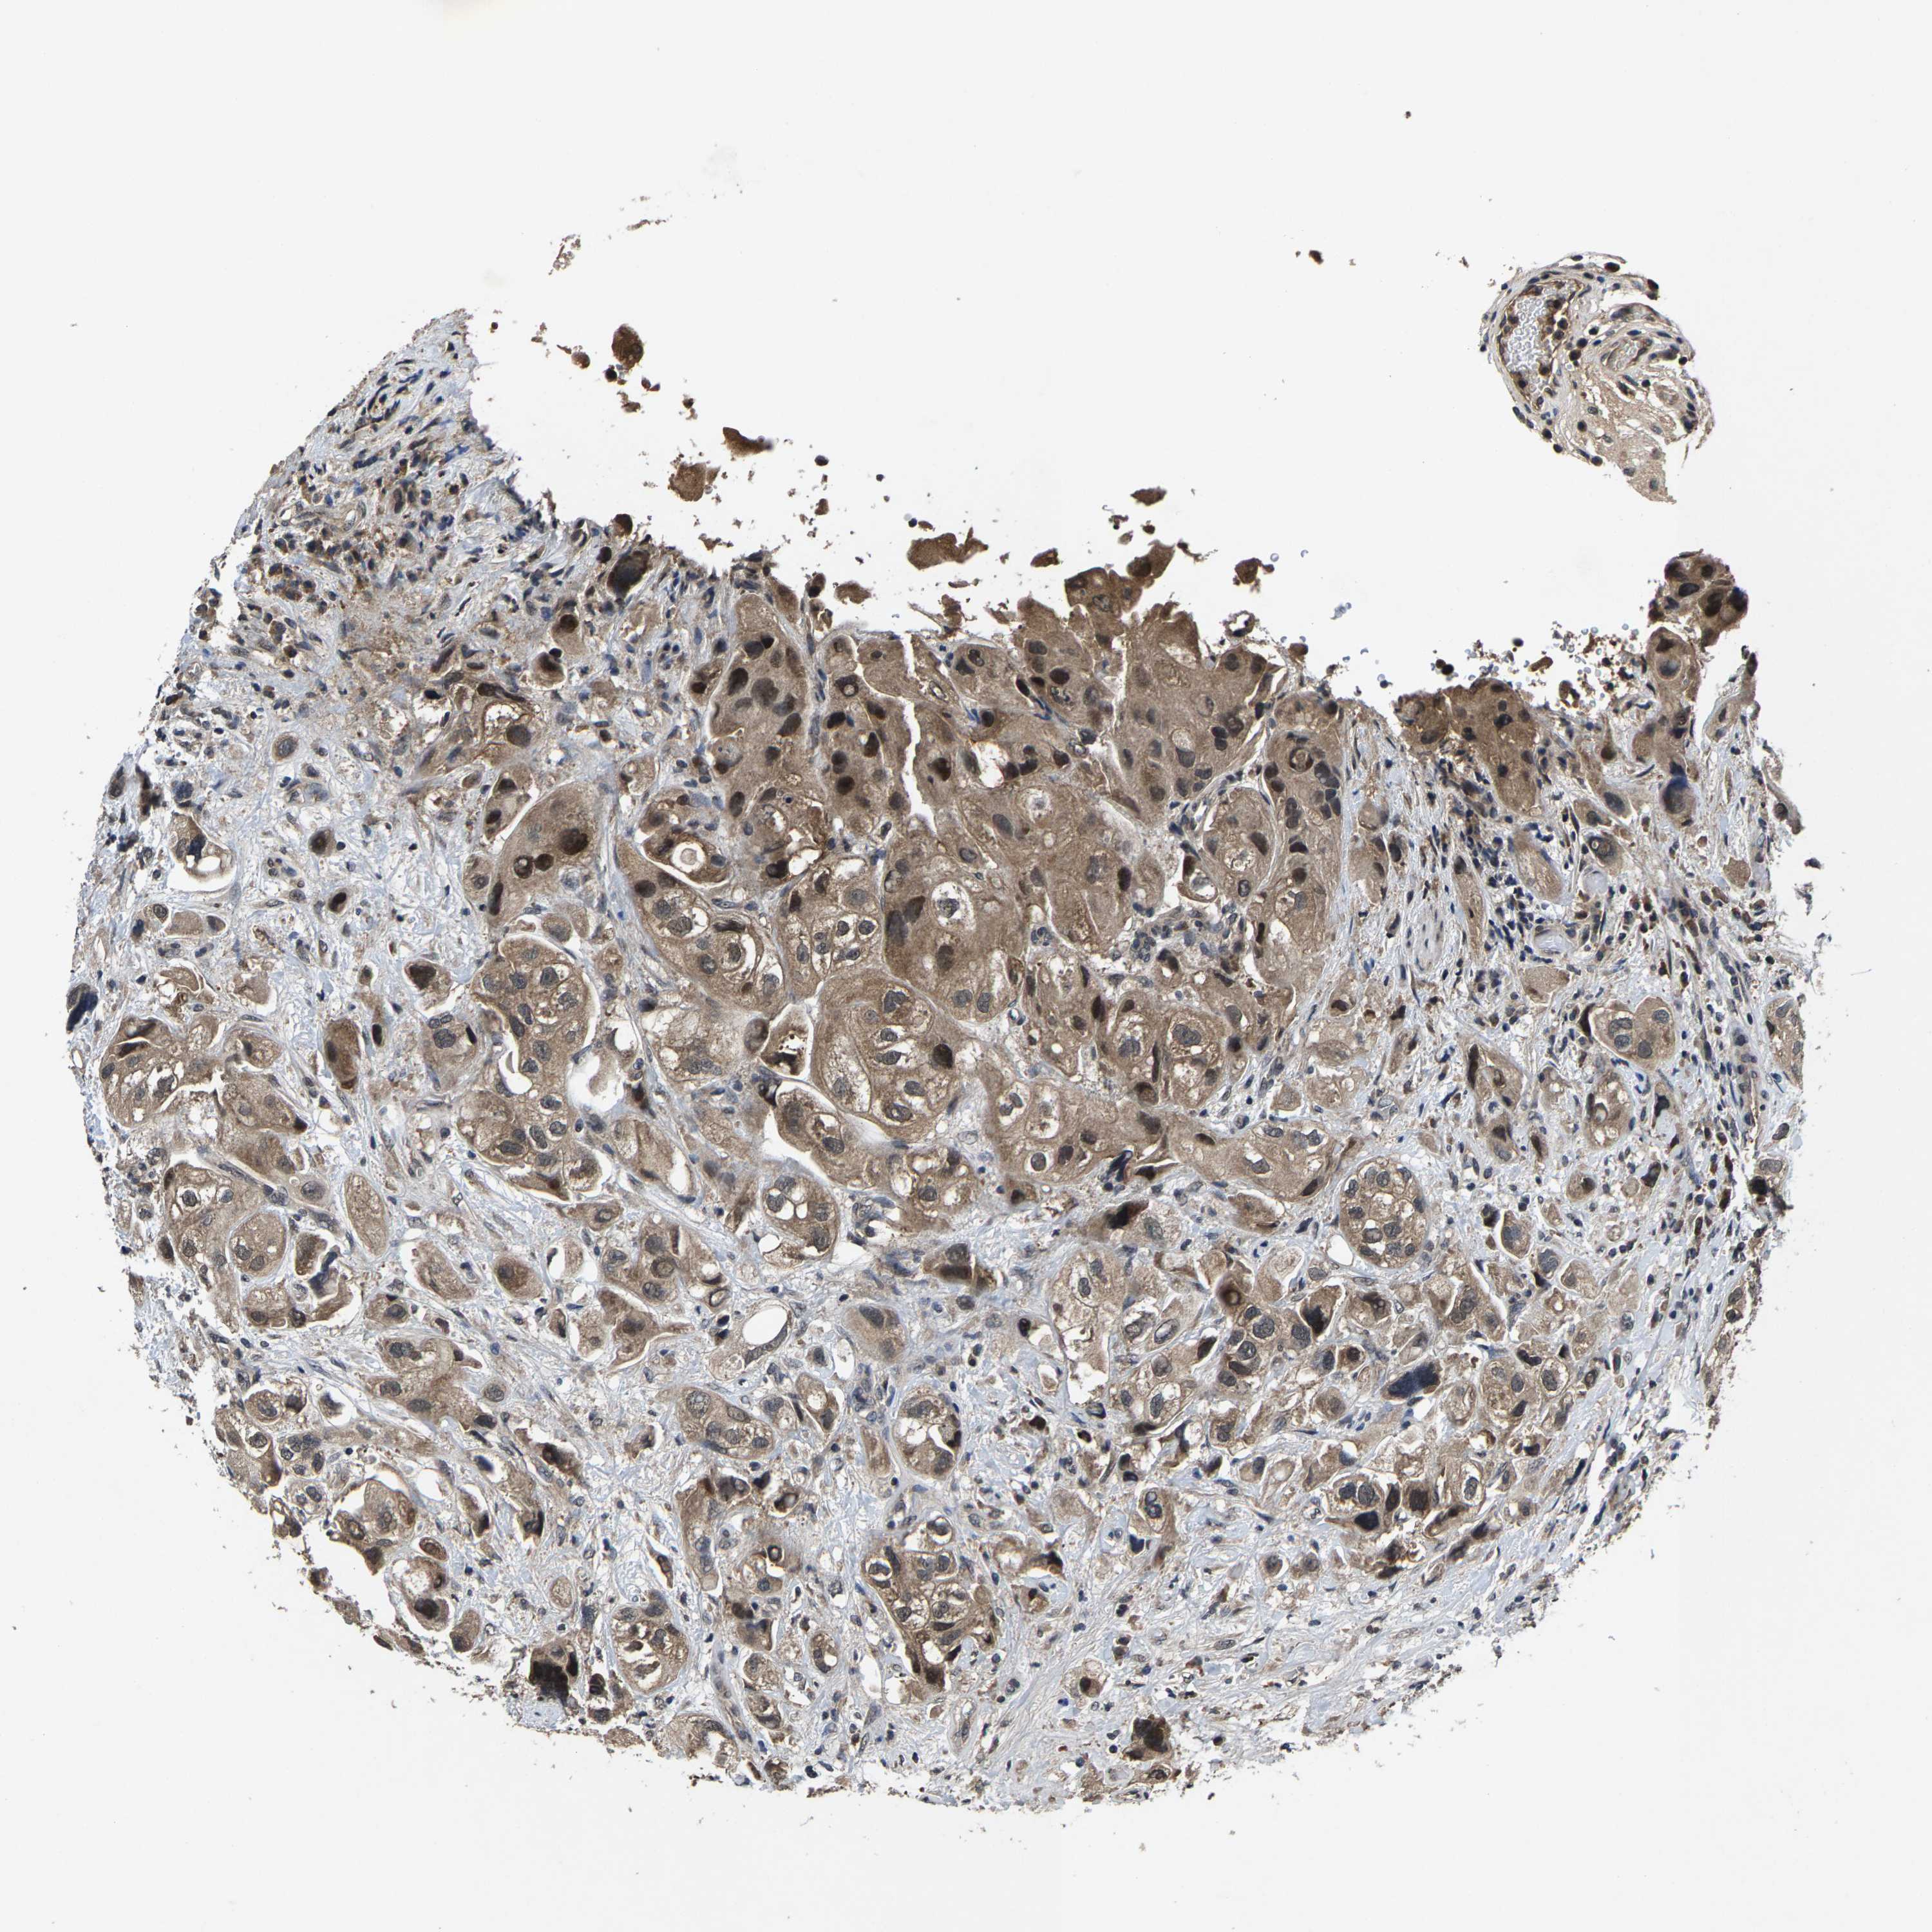

UROTHELIAL CANCER - Protein expressioni

A mouse-over function shows sample information and annotation data. Click on an image to view it in a full screen mode. Samples can be filtered based on level of antibody staining by selecting one or several of the following categories: high, medium, low and not detected. The assay and annotation is described here.

Note that samples used for immunohistochemistry by the Human Protein Atlas do not correspond to samples in the TCGA dataset.

Antibody stainingi

Antibody staining in the annotated cell types in the current human tissue is reported as not detected, low, medium, or high, based on conventional immunohistochemistry profiling in selected tissues. This score is based on the combination of the staining intensity and fraction of stained cells.

Each image is clickable and will lead to virtual microscopy that enables deeper exploration of all samples and also displays staining intensity scores, fraction scores and subcellular localization as well as patient and tissue information for each sample.

Antibody HPA002548

Antibody CAB022718

Staining

High

Medium

Low

Not detected

Intensity

Strong

Moderate

Weak

Negative

Quantity

>75%

75%-25%

<25%

None

Location

Nuclear

Cytoplasmic/membranous

Cytoplasmic/membranous,nuclear

Urothelial carcinoma, High grade

Urothelial carcinoma, Low grade

Adenocarcinoma, NOS